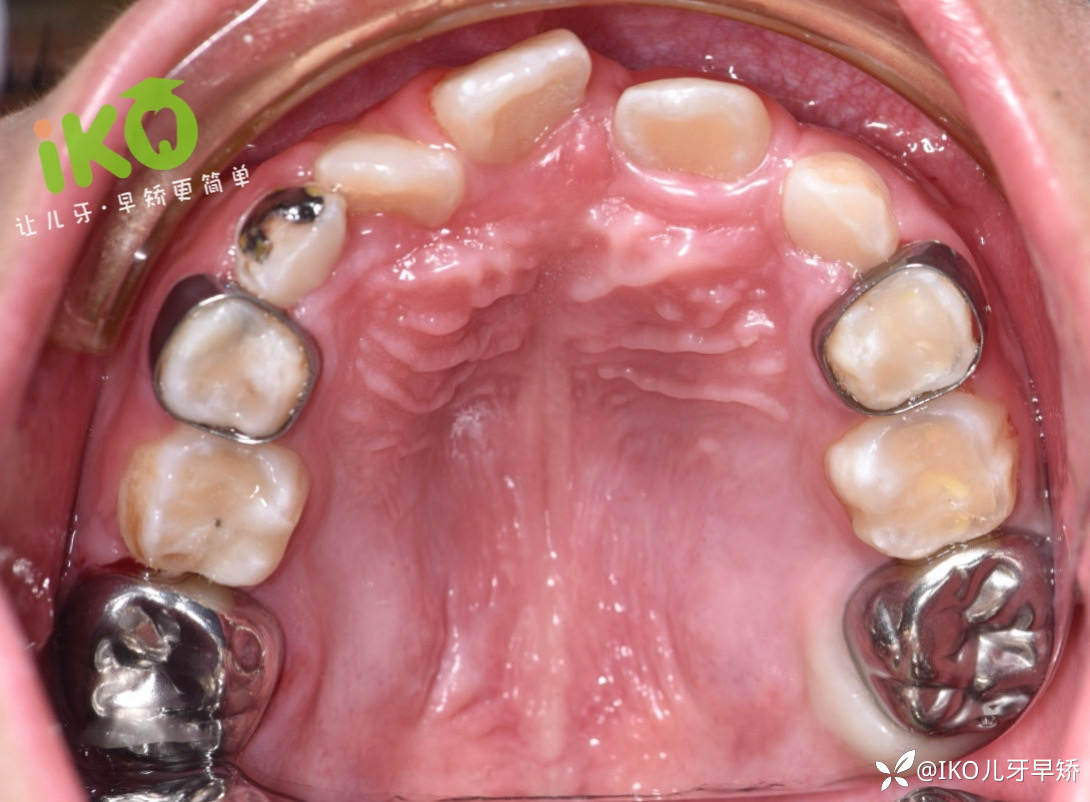

临床实战病例分享 · (一)

临床症状描述:

74残冠,75近中中度龋坏。

临床操作方案:

74局部麻醉下拔除,75去龋充填,然后用75做为基牙(固位体),做丝圈式间隙保持器。

详细临床操作步骤: ↓

75·补牙

步骤一:75局麻下上橡皮障,进行去龋坏充填。

步骤二: 局麻下拔除74,然后在75和36之间放入分牙圈⭕,3到5日后用金属冠作为基牙(固位体)进行取模操作。

步骤三: 将模型寄到加工厂定做 → 金属冠式·间隙保持器;最后收到间隙保持进行口内佩戴。

临床佩戴结束🔚·口内照/侧面照